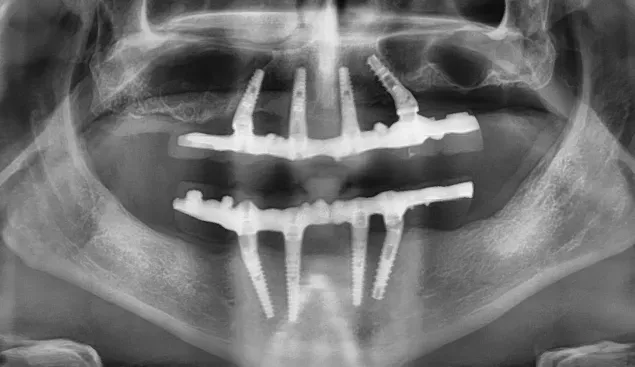

Le immagini radiografiche che seguono testimoniano alcune delle tante soluzioni tecniche che ho utilizzato per le arcate a carico immediato nel corso della mia carriera. Ogni caso presenta sfide diverse e richiede un approccio personalizzato.